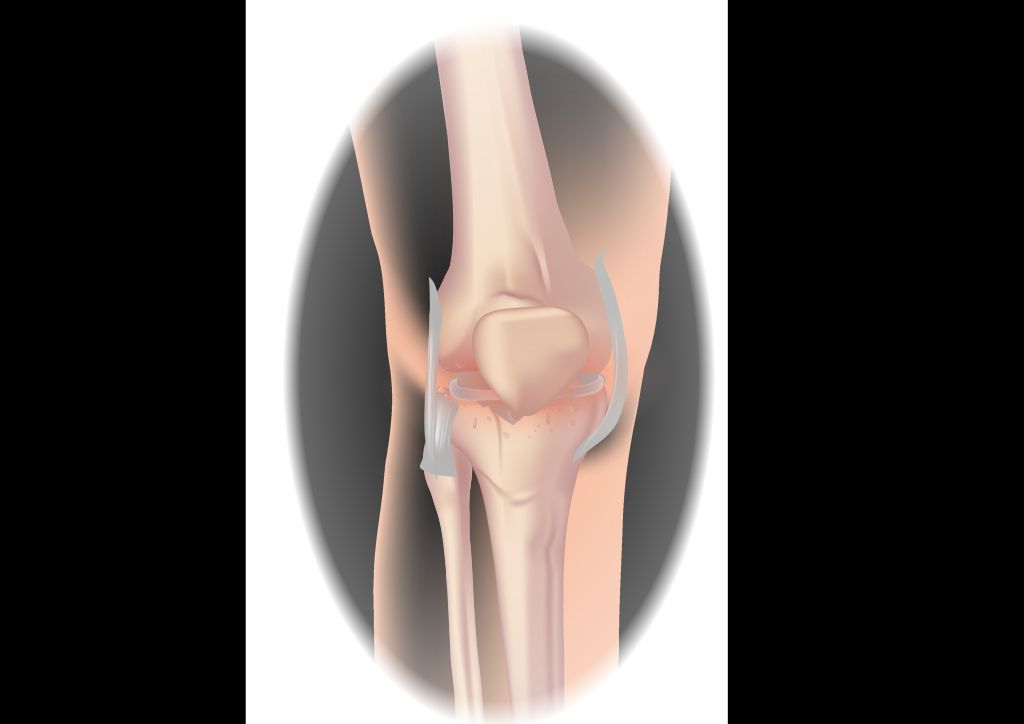

Pathophysiology of OA Knee

Osteoarthritis of the knee is a common degenerative joint disease characterized by the breakdown of cartilage, bone changes, and joint inflammation. It is often the result of wear and tear on the knee joint, leading to pain, stiffness, and reduced mobility. The progression of OA knee involves a complex interplay of mechanical, genetic, and environmental factors. Physiotherapy plays a crucial role in managing OA knee, addressing weakness, stability, movement, and balance. It is an integral part of the comprehensive treatment plan for OA knee, aiming to improve function and reduce pain.